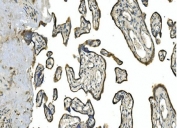

Carbonic anhydrase 13 is a protein that in humans is encoded by the CA13 gene. Carbonic anhydrases (CAs) are a family of zinc metalloenzymes that catalyze the interconversion between carbon dioxide and water and the dissociated ions of carbonic acid (i.e. bicarbonate and hydrogen ions).

Amino acids RLSWGYREHNGPIHWKEFFP from the human protein were used as the immunogen for the CA13 antibody.